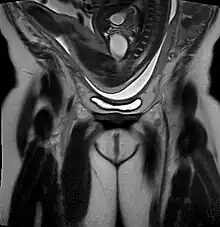

Breech birth position seen on MRI

As in labour with a baby in a normal head-down position, uterine contractions typically occur at regular intervals and gradually the cervix begins to thin and open.[31] In the more common breech presentations, the baby's bottom (rather than feet or knees) is what is first to descend through the maternal pelvis and emerge from the vagina.[23]